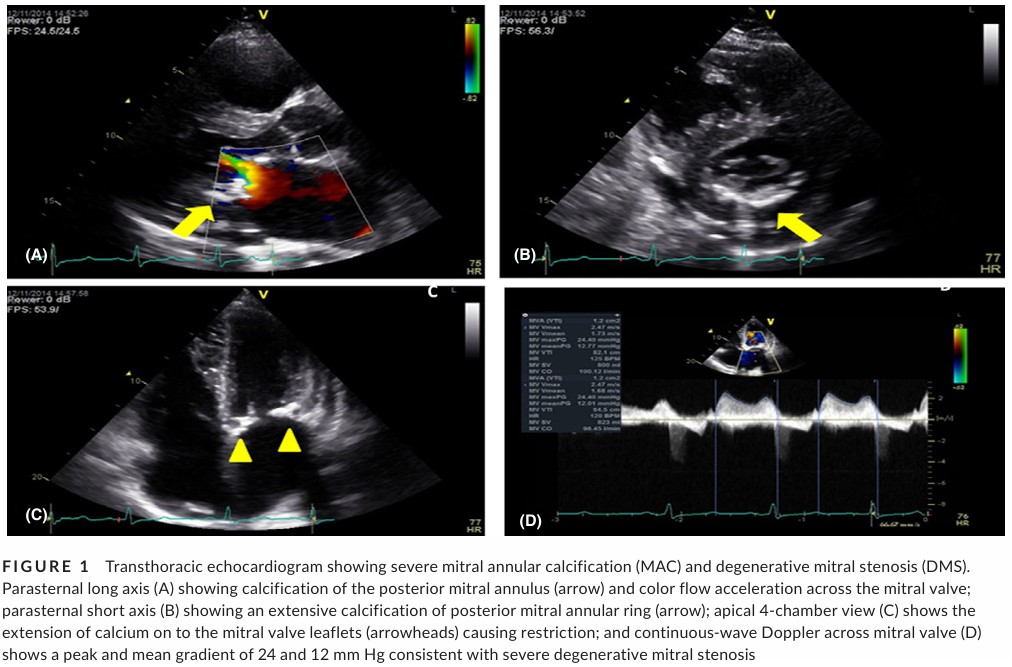

Estenose mitral degenerativa foi definida como aquela associada à presença de calcificação severa do anel mitral com acometimento dos folhetos valvares resultando em restrição de mobilidade e obstrução do influxo mitral.